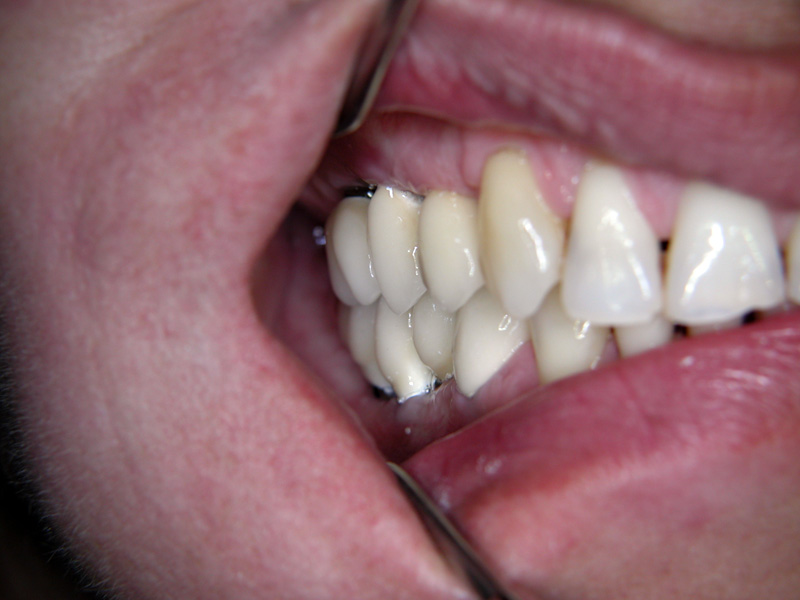

Implante - Galerie Foto

Caz I